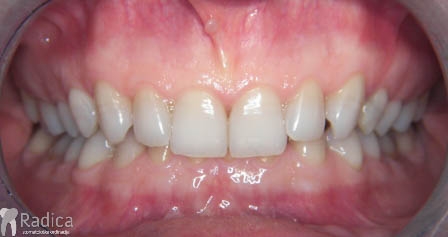

Slučaj 1: ispravljanje otvorenog zagriza i kompresije Invisalign full terapijom

Slučaj 2: ispravljanje kompresije Invisalign full terapijom- u ovom slučaju je izvađen jedan donji sjekutić

Slučaj 3: ispravljanje kompresije Invisalign full terapijom

Slučaj 4: ispravljanje kompresije Invisalign full terapijom

Slučaj 5: ispravljanje kompresije i križnog zagriza Invisalign full terapijom

Slučaj 6: ispravljanje kompresije i dubokog zagriza Invisalign full terapijom

Slučaj 7: ortodontska predprotetska terapija Invisalign full